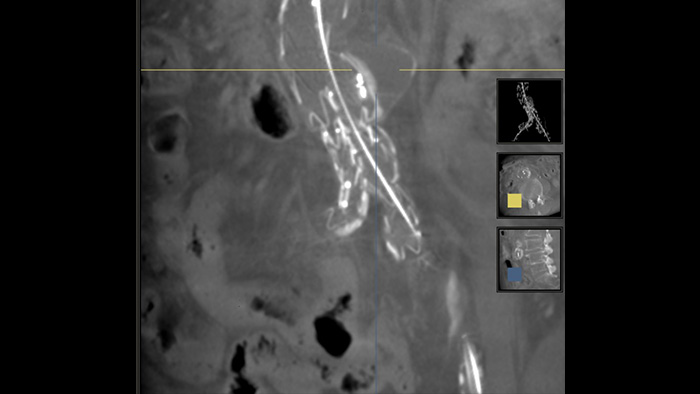

SmartCT Soft Tissue is an X-ray acquisition technique that generates a CT-like visualisation of soft tissue in relation to other structures during procedures – all controlled via the touch screen at the table. You can use the CT-like images to assess soft tissue, bone structure and stent deployment before, during and after interventional procedures. This technique is particularly useful to check for complications after (complex) EVAR procedures.